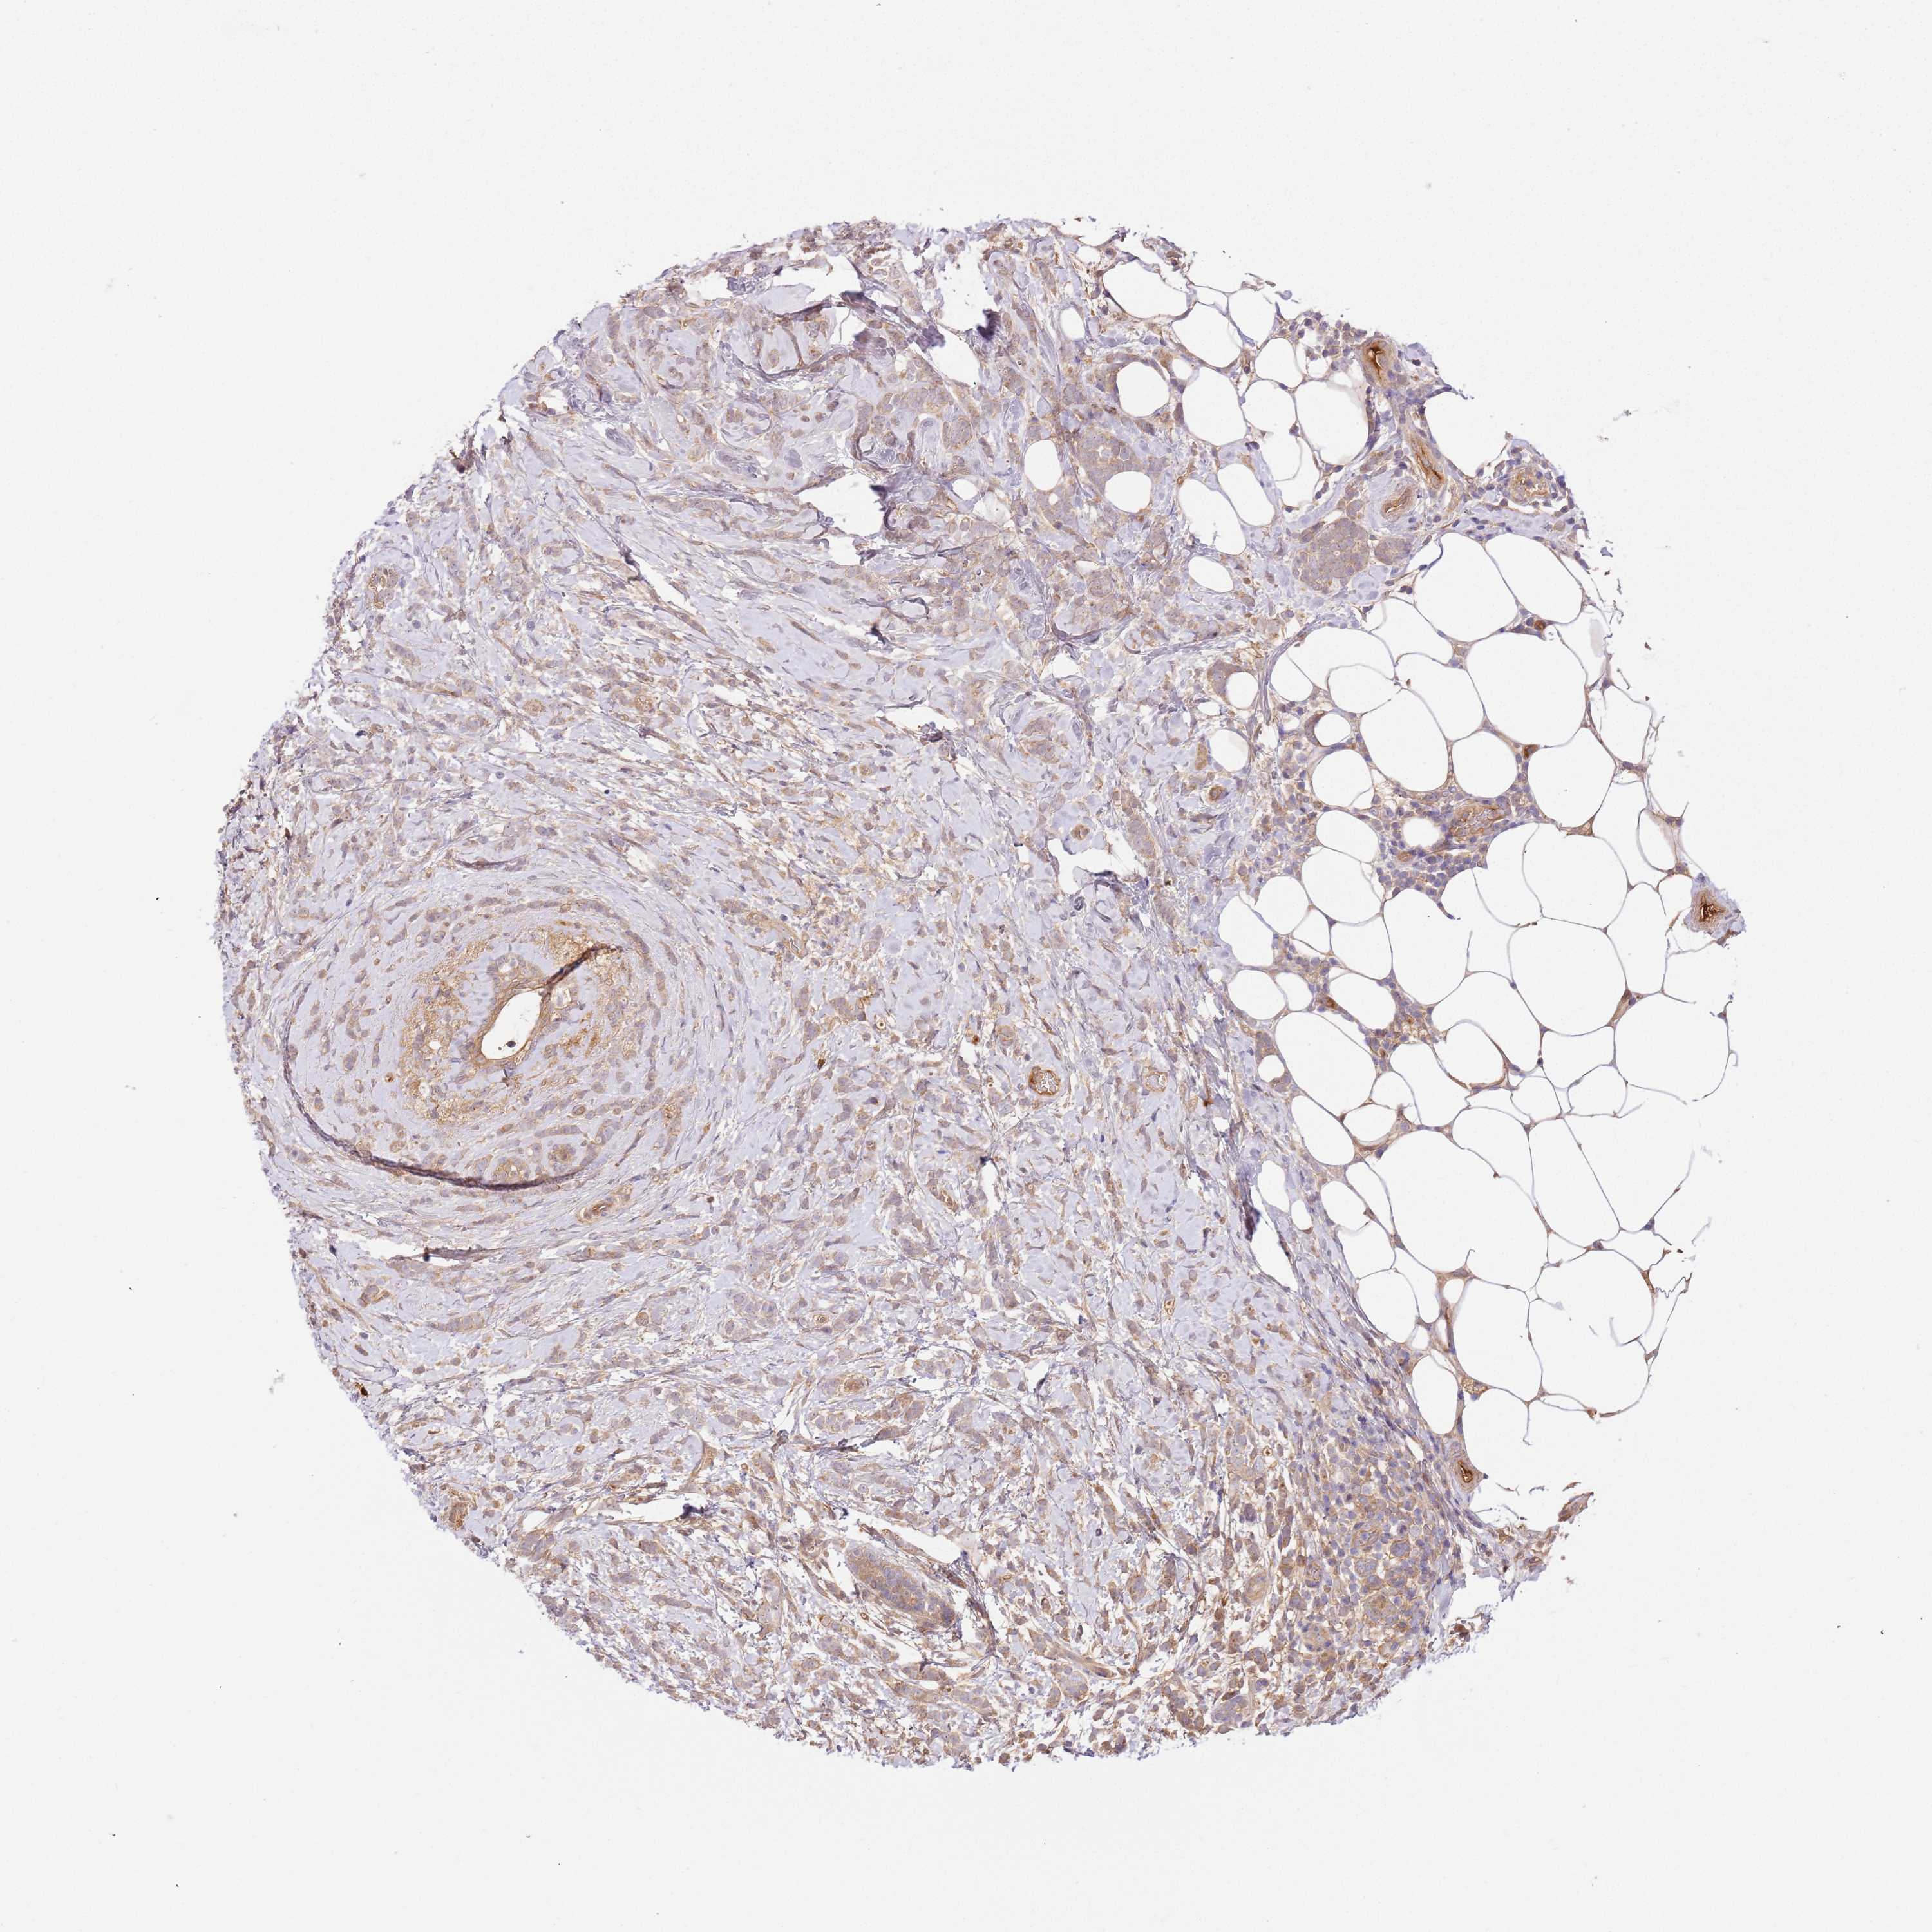

CANCER BREAST CANCER Show tissue menu

BRCA TCGA BRCA VALIDATION PROTEIN EXPRESSION